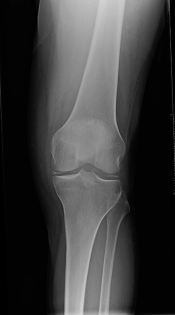

Chondrocalcinosis & Pseudogout Gepost op 21 september 2017 door netwerkvsseh Back to Basics: Chondrocalcinosis & Pseudogout@emdaily.cooperhealth.org Dit delen: Delen op X (Opent in een nieuw venster) X Share op Facebook (Opent in een nieuw venster) Facebook Delen op LinkedIn (Opent in een nieuw venster) LinkedIn E-mail een link naar een vriend (Opent in een nieuw venster) E-mail Afdrukken (Opent in een nieuw venster) Print Vind-ik-leuk Aan het laden... Gerelateerd